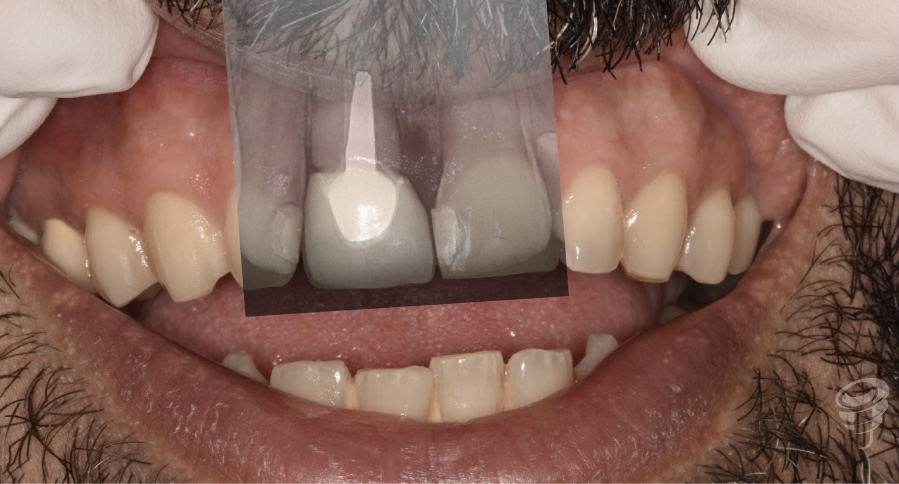

Caso Clínico | Rehabilitación Estética Integral con implante inmediato, injerto óseo y de tejido conectivo y carillas de cerámica en incisivo central superior fracturado

- Caso clínico: Paciente masculino de 45 años con fractura irreparable del incisivo central superior derecho (11) previamente tratado con una endodoncia y unión colado, fracturado por trauma oclusal. Se realizó extracción atraumática, colocación de implante inmediato, injerto óseo xenogénico mezclado con hueso antólogo del fresado, e injerto de tejido conectivo subepitelial para optimizar el perfil de emergencia. A los 4 meses se colocó corona implanto-soportada de zirconio y carillas de disilicato de litio en dientes 12 y 21.

Figura 4

- Impresión convencional para realizar un encerado diagnóstico estético y posteriormente una realización de réplica del perfil de emergencia con la técnica de Hinds, para solapar una medida convencional con una digital (escáner intraoral).